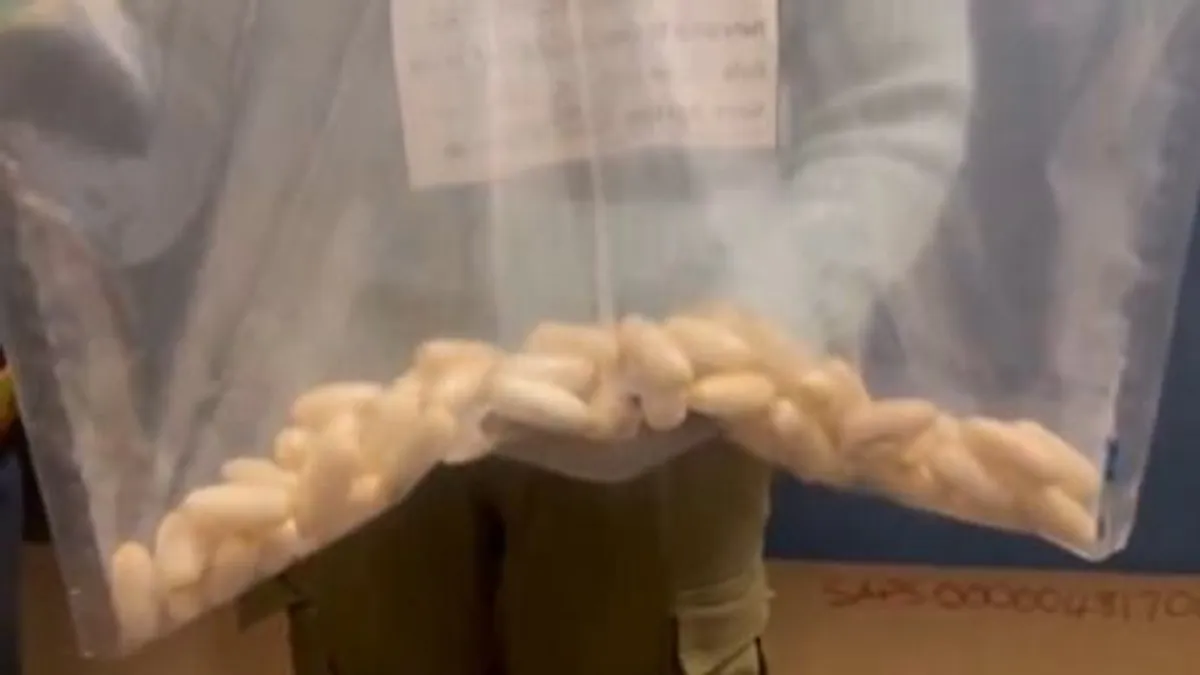

Félelmetes! Az orvosok is sokkot kaptak attól, ami a kislány gyomrából előkerült

A 9 éves lány ártalmatlannak tűnő szokása nagy bajt okozott.